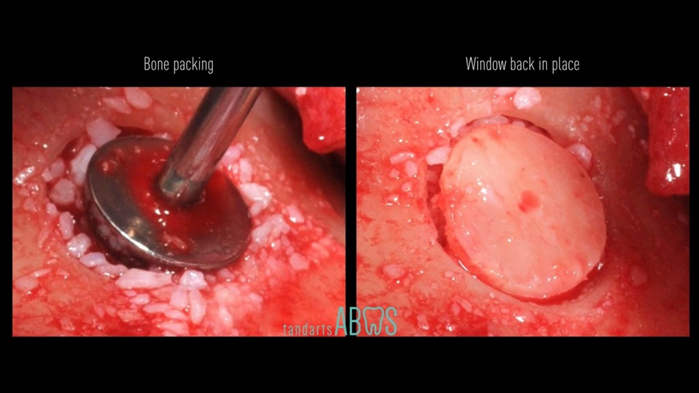

Clinical case: Installation of dental implants in complicated anatomic conditions using crest lifting methods

- Courtesy of Dr.Alexander Lysov, Russia -

Keywords

AnyRidge, complicated anatomic conditions, crest lift, MICA Kit, Dr. Alexander Lysov, bone regeneration, GBR, #26, maxillary posterior

Products:

AnyRidge implant system, MICA Kit